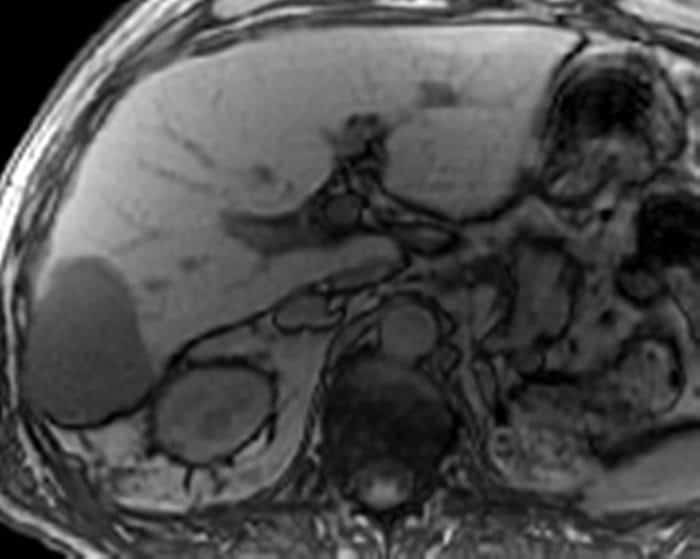

U máu gan

» Thông tin: Nam giới – 70 tuổi.

» Lâm sàng: Tiền sử ung thư thận.